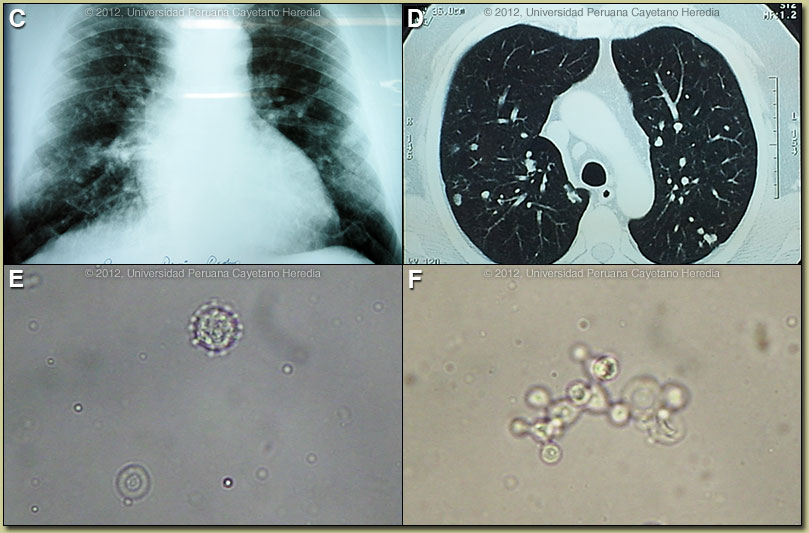

Discussion: Chest X-ray and CT are shown [Images C, D]. The diagnosis was made by simple KOH preparation of a mucosal scraping, which showed typical spherical cells 10-40 microns in diameter with a thick birefrigent cell wall [Image E]. Image F shows a budding yeast surrounded by several peripheral buds with typical narrow necks. When completely surrounded by such buds a so-called “pilot-wheel” pattern occurs. Direct scrapings will be positive in up to 90% of cases of paracoccidioidomycosis with oral lesions. Sputum AFB stain was negative. Biopsies are not necessary in characteristic clinical cases with positive scrapings.